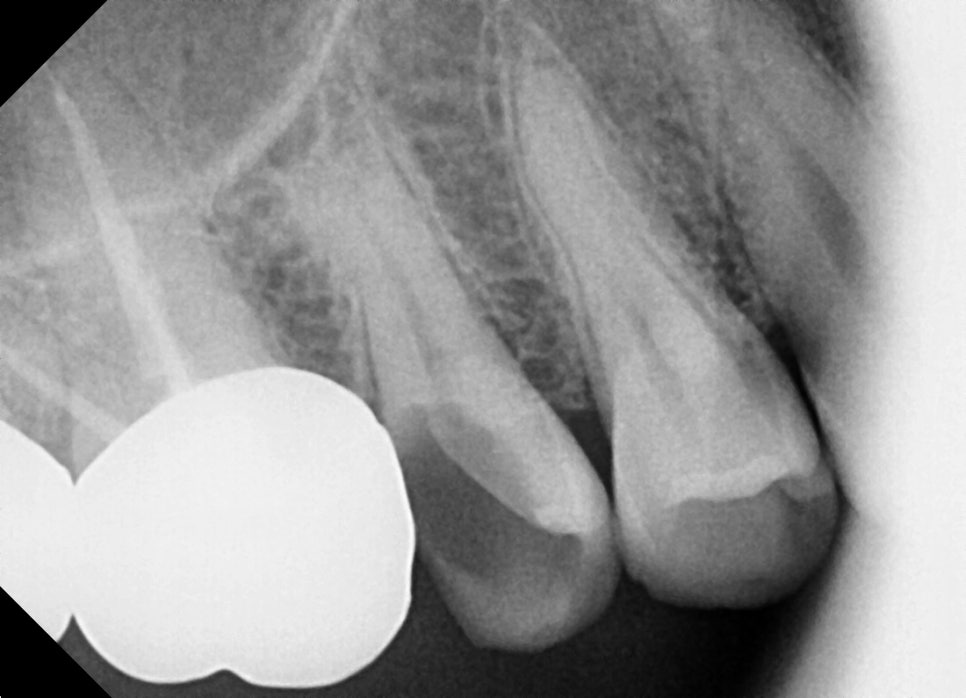

At the initial visit

The right tooth broke, and it feels sensitive and painful.

After checking the X-ray, we found that the cavity was so severe that the tooth

had come in broken.

When a molar breaks like this,

root canal treatment is necessary.

<Before treatment / After treatment>